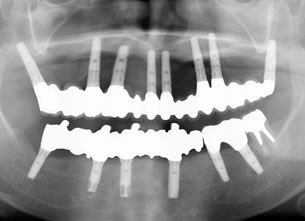

症例1 : 上下顎無菌顎症例

69歳、男性。

• 上顎は両側サイナスリフトと同時に即時荷重を行った。

• 下顎は抜歯即時埋入即時荷重を行った。

• 最終補綴物は、チタンのP.I.B.とM.B.のコンビネーションで修復した。

• 本症例の要旨は第39回日本口腔インプラント学会(大阪)にて症例報告した。